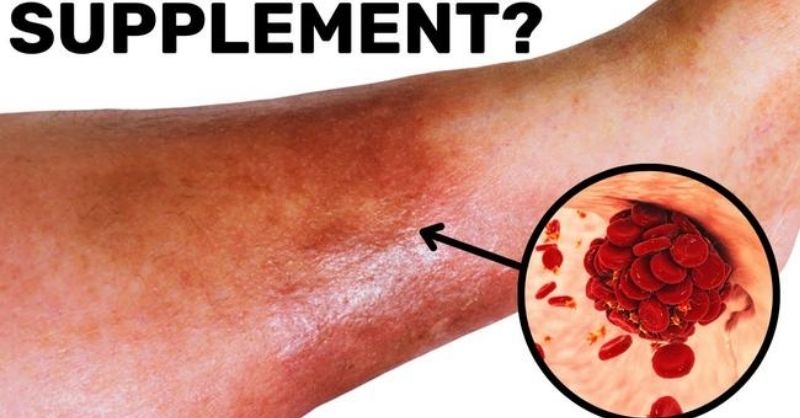

One tablespoon a day and bl00d clots disappear forever!

If you’re over 40, you may be carrying a silent danger inside your veins: blood clots. They affect millions of people each year and can trigger life-threatening conditions...